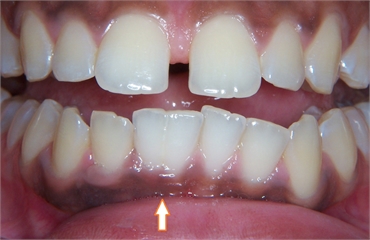

Gemination can be described as teeth ‘twinning’. In dental context, gemination refers to a developmental irregularity in which a single tooth germ divides resulting in a bifid crown on a single root, that is, two teeth develop together from a single tooth bud. The two parts of the double tooth will be exact images of each other. It is seen as a cleft crown on x-rays where the radiopaque enamel outlines the invagination.

Gemination is very often confused with fusion (two teeth unite to become one) but may be differentiated based on the fact that the number of teeth in fusion is less than the actual number of teeth that should be present in the mouth. The main difference lies in the fact that a tooth with gemination will have a single root and canal whereas in fused teeth, there will be independent roots and canals.

They are more commonly observed in baby teeth than in the permanent teeth. They most frequently occur in the primary upper incisors.